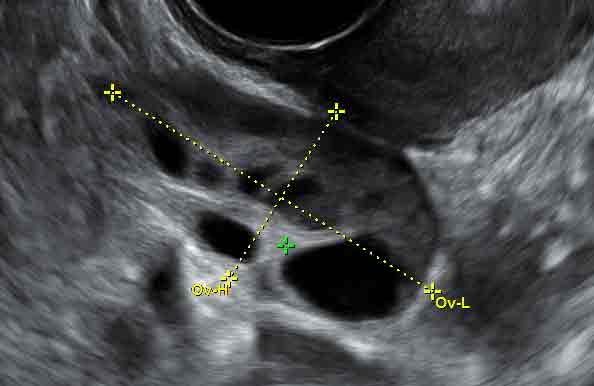

Фолликулометрия — это метод УЗИ-диагностики, с помощью которого проводится мониторинг созревания фолликулов. Основная задача фолликулометрии — определение подходящего для зачатия дня, вычисление даты овуляции, выявление нарушений менструального цикла, оценка необходимости стимуляции овуляции и контроль развития эндометрия.

Фолликулометрия — один из самых эффективных способов определения овуляции, рекомендуемый женщинам с бесплодием или нарушениями менструального цикла. Процедура аналогична стандартному УЗИ, используемому в акушерстве и гинекологии.